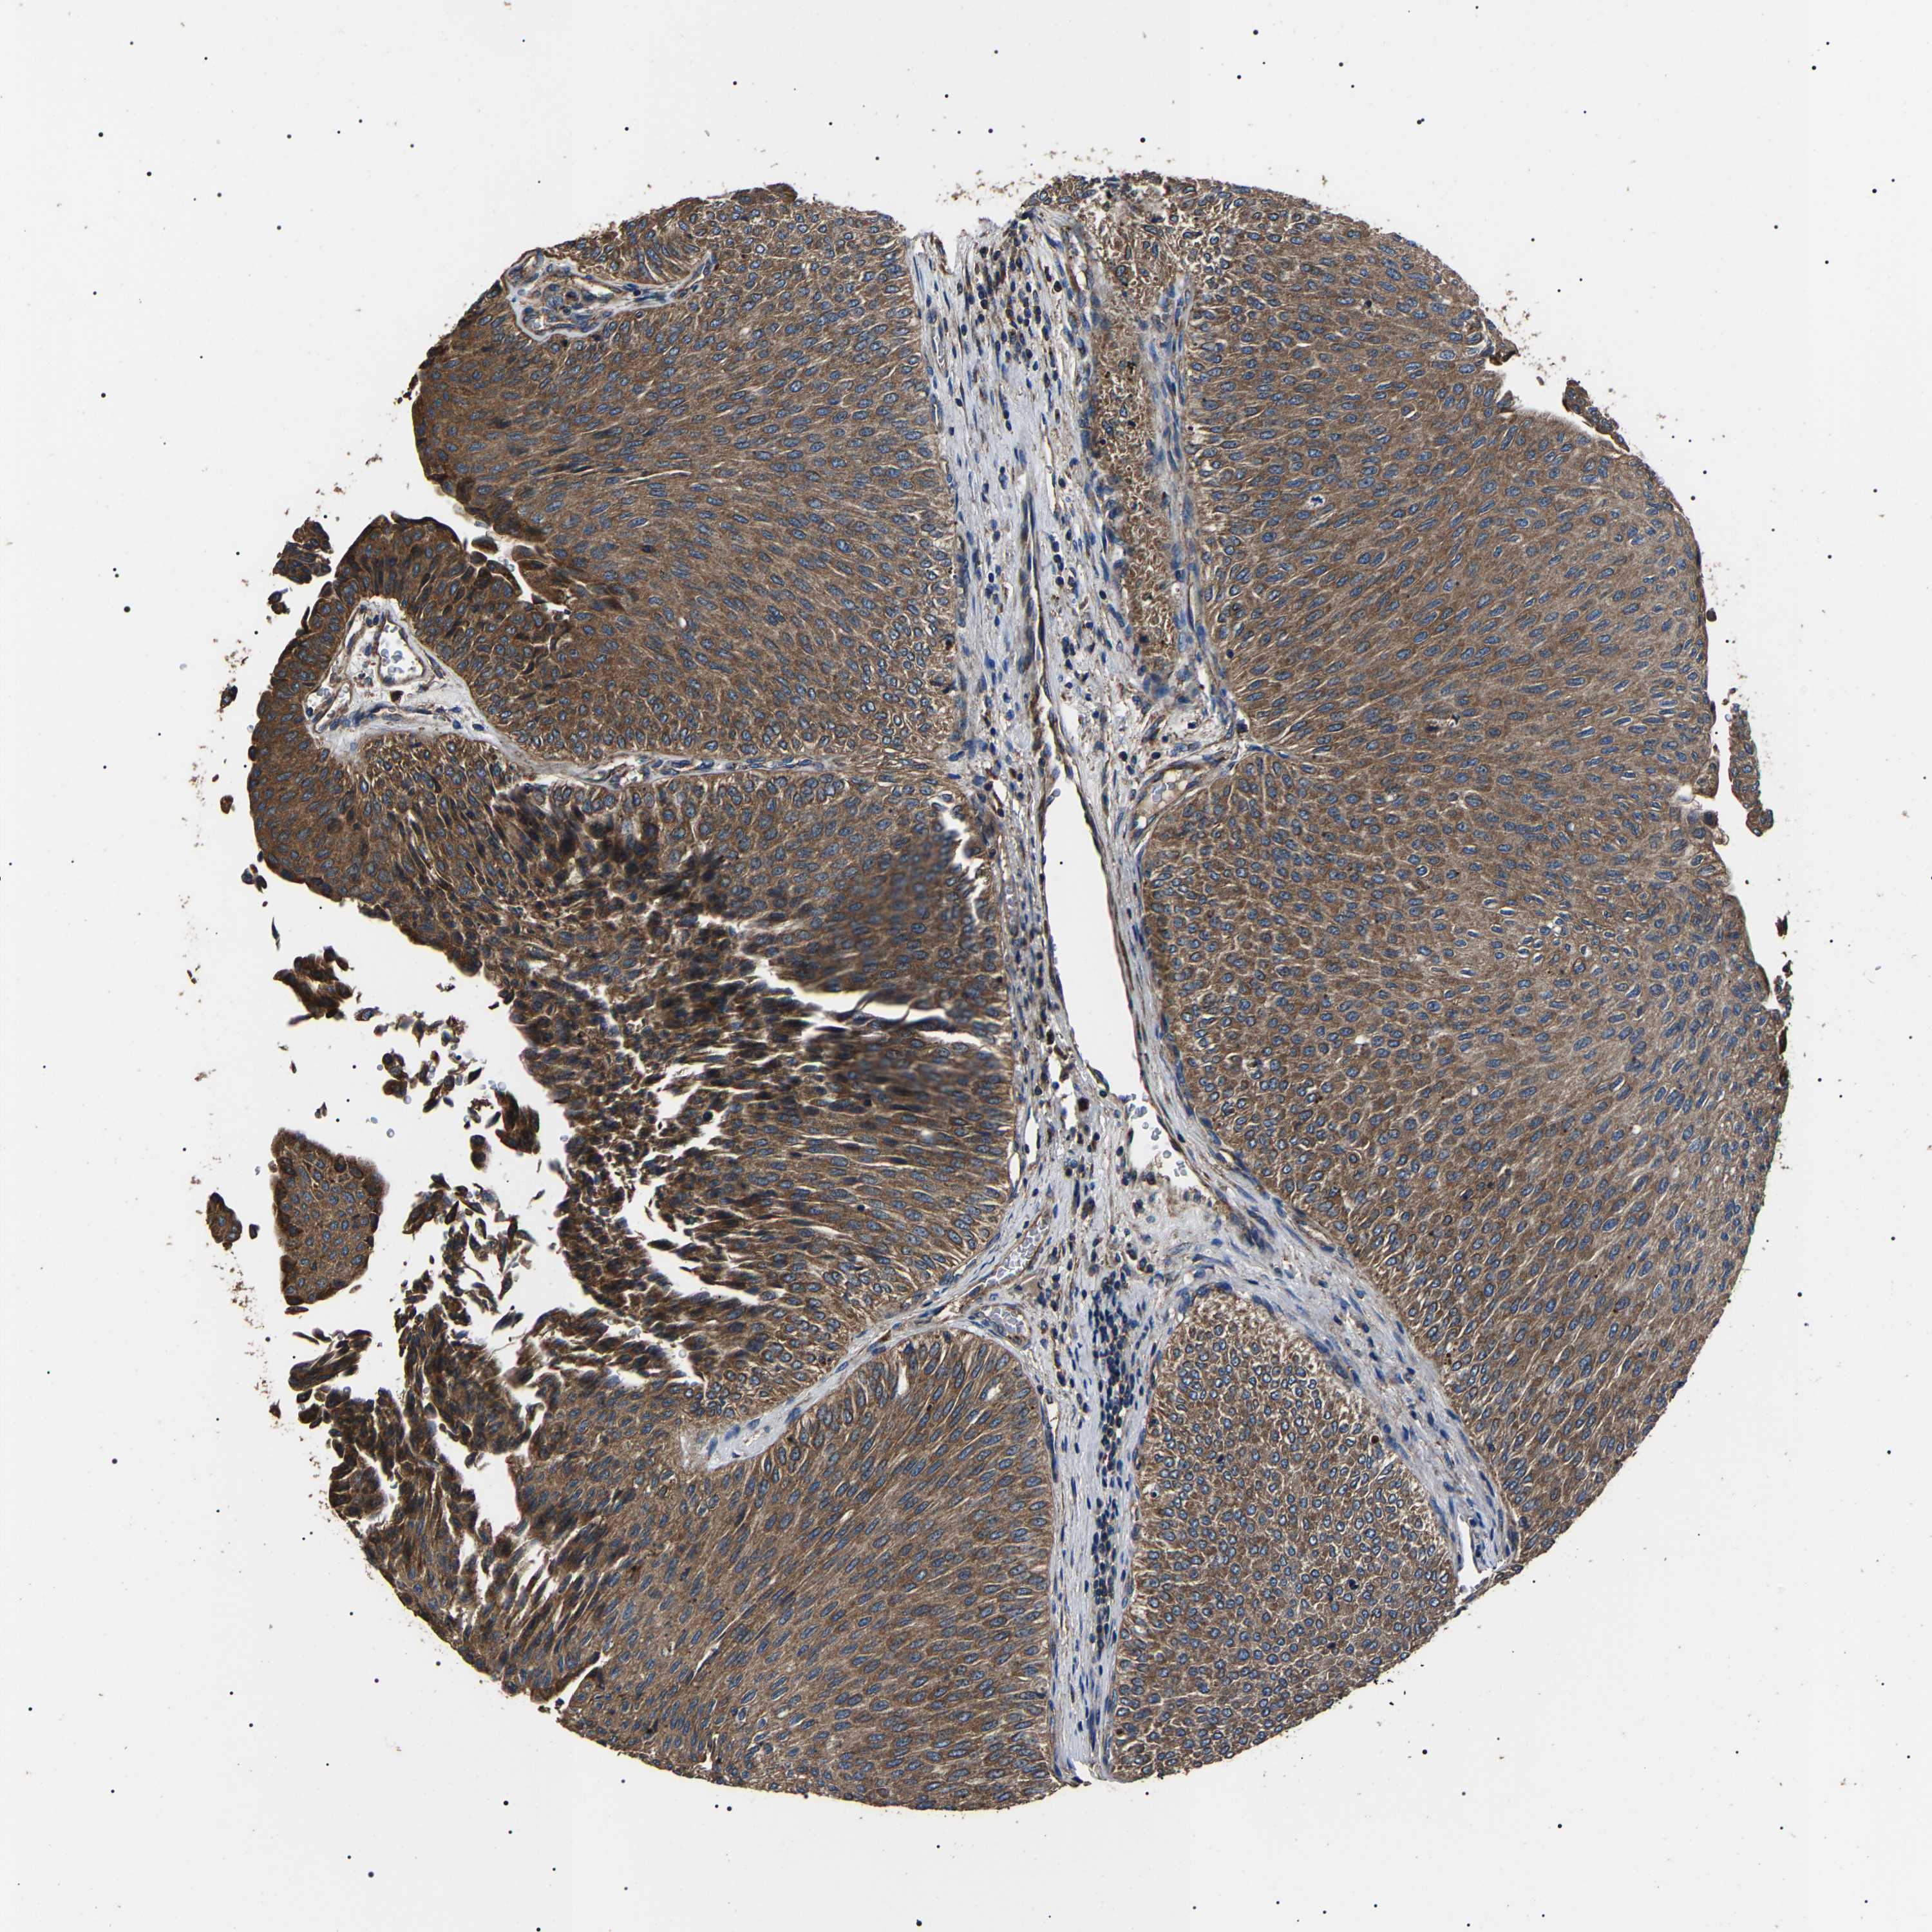

UROTHELIAL CANCER - Protein expressioni

A mouse-over function shows sample information and annotation data. Click on an image to view it in a full screen mode. Samples can be filtered based on level of antibody staining by selecting one or several of the following categories: high, medium, low and not detected. The assay and annotation is described here.

Antibody stainingi

Antibody staining in the annotated cell types in the current human tissue is reported as not detected, low, medium, or high, based on conventional immunohistochemistry profiling in selected tissues. This score is based on the combination of the staining intensity and fraction of stained cells.

Each image is clickable and will lead to virtual microscopy that enables deeper exploration of all samples and also displays staining intensity scores, fraction scores and subcellular localization as well as patient and tissue information for each sample.

Antibody HPA018447

Staining

High

Medium

Low

Not detected

Intensity

Strong

Moderate

Weak

Negative

Quantity

>75%

75%-25%

<25%

None

Location

Nuclear

Cytoplasmic/membranous

Cytoplasmic/membranous,nuclear

Urothelial carcinoma, Low grade

Urothelial carcinoma, High grade